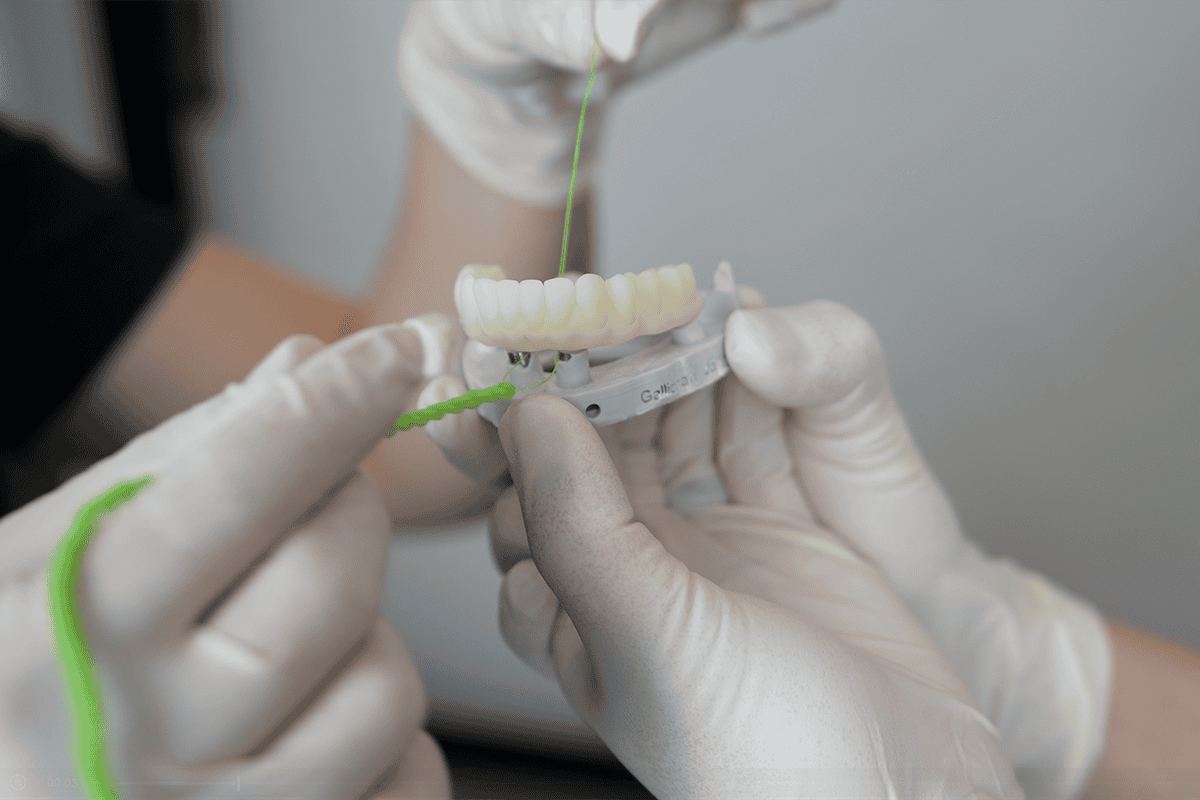

We are here to support you regardless of where you are in your dental health journey, whether that’s with preventive care or reconstructive options like porcelain veneers, All-On-4 dental implants, or full mouth reconstruction.

This may involve treatments such as fillings or crowns, and in more severe cases, restorative procedures like porcelain veneers or full mouth reconstruction. However, cosmetic treatments are only offered once the health and condition of your teeth are restored.

When it comes to our All-On-4 dental implants, we conduct thorough bone scans for all patients to determine whether they have enough healthy bone structure to support the implants. In cases where periodontitis has progressed too far and the jawbone has eroded, alternative treatments may need to be considered. This makes it all the more important to catch and treat gum disease early to increase the chances of a successful outcome.

If your decay has already progressed significantly, don’t lose hope. At Advanced Dental Artistry, we offer full mouth reconstruction for patients who need extensive restorative work. Our goal is to not only improve the health of your teeth and gums but to give you a beautiful smile you can be proud of.